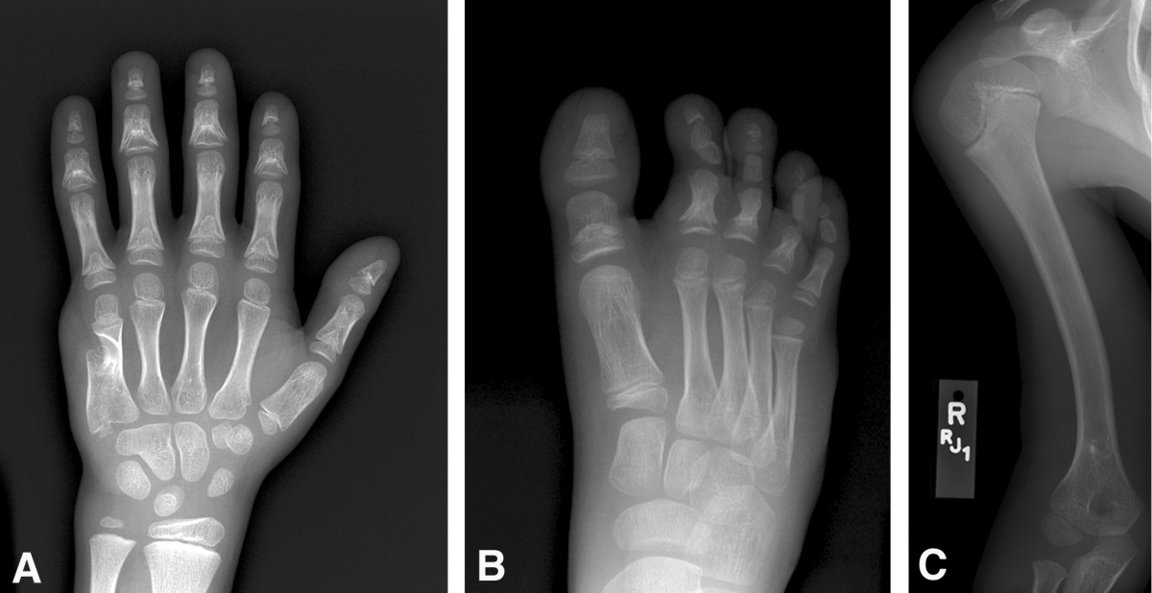

Brachyphalangia

Brachyphalangia a hypophalangia patria medzi vrodené vývojové chyby skeletu končatín. Pri tomto ochorení sa jedná vždy o vrodený defekt postihujúci články prstov na končatinách človeka. V prípade brachyfalangie ide o skrátenie jedného alebo viac článkov prstov, v prípade hypofalangie ide o znížený počet článkov prstov. S týmito chybami úzko súvisí pojem brachydaktylia, čo je dedičná malformácia postihujúca dĺžku prstov - abnormálne krátke prsty a pojem hypodaktýlia - menší počet prstov.

• abnormálne krátky článok prsta na ktorejkoľvek končatine (brachyphalangie)

• znížený počet článkov prstov na ktorejkoľvek končatine (hypophalangie)

• abnormálne krátke prsty (brachydaktylie)

• znížený počet prstov (hypodaktylie)